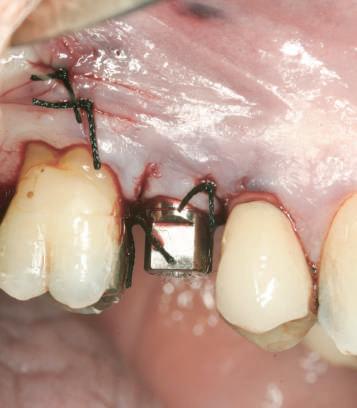

Figurile 8. Cu ajutorul unui model de ţesut moale şi al unei sonde parodontale, se poate localiza cu precizie profunzimea marginii bontului. 9, 10. Materialul pentru ţesutul moale reprezentat pe model permite adaptarea contururilor subgingivale ale bontului la conturul ideal (fig. 9), şi când se îndepărtează, oferă acces la interfaţa analogului (fig. 10).

Cu scopul de a oferi acces pentru replica implantului în cursul procesului de fabricaţie, pentru restaurările implantare este necesar un model al ţesutului moale. Se utilizează un material siliconic de adiţie sau de condensaţie pentru a reproduce contururile ţesuturilor moi din jurul treimii coronare a replicii implantului.

În cursul etapei de concepere şi de fabricaţie a restaurării, îndeosebi la FPD, este esenţială o vedere clară asupra interfeţei bont-replica implantului pentru a se asigura faptul că toate componentele sunt complet aşezate şi a verifica adaptarea restaurării. În plus, aceasta permite tehnicianului să reproducă sau să sculpteze în materialul siliconic profilul ideal de emergenţă dintre implant şi marginea gingivală, care se poate replica apoi în cursul fabricării bontului (fig. 9, 10).